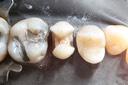

Kyle Chock #2 prep